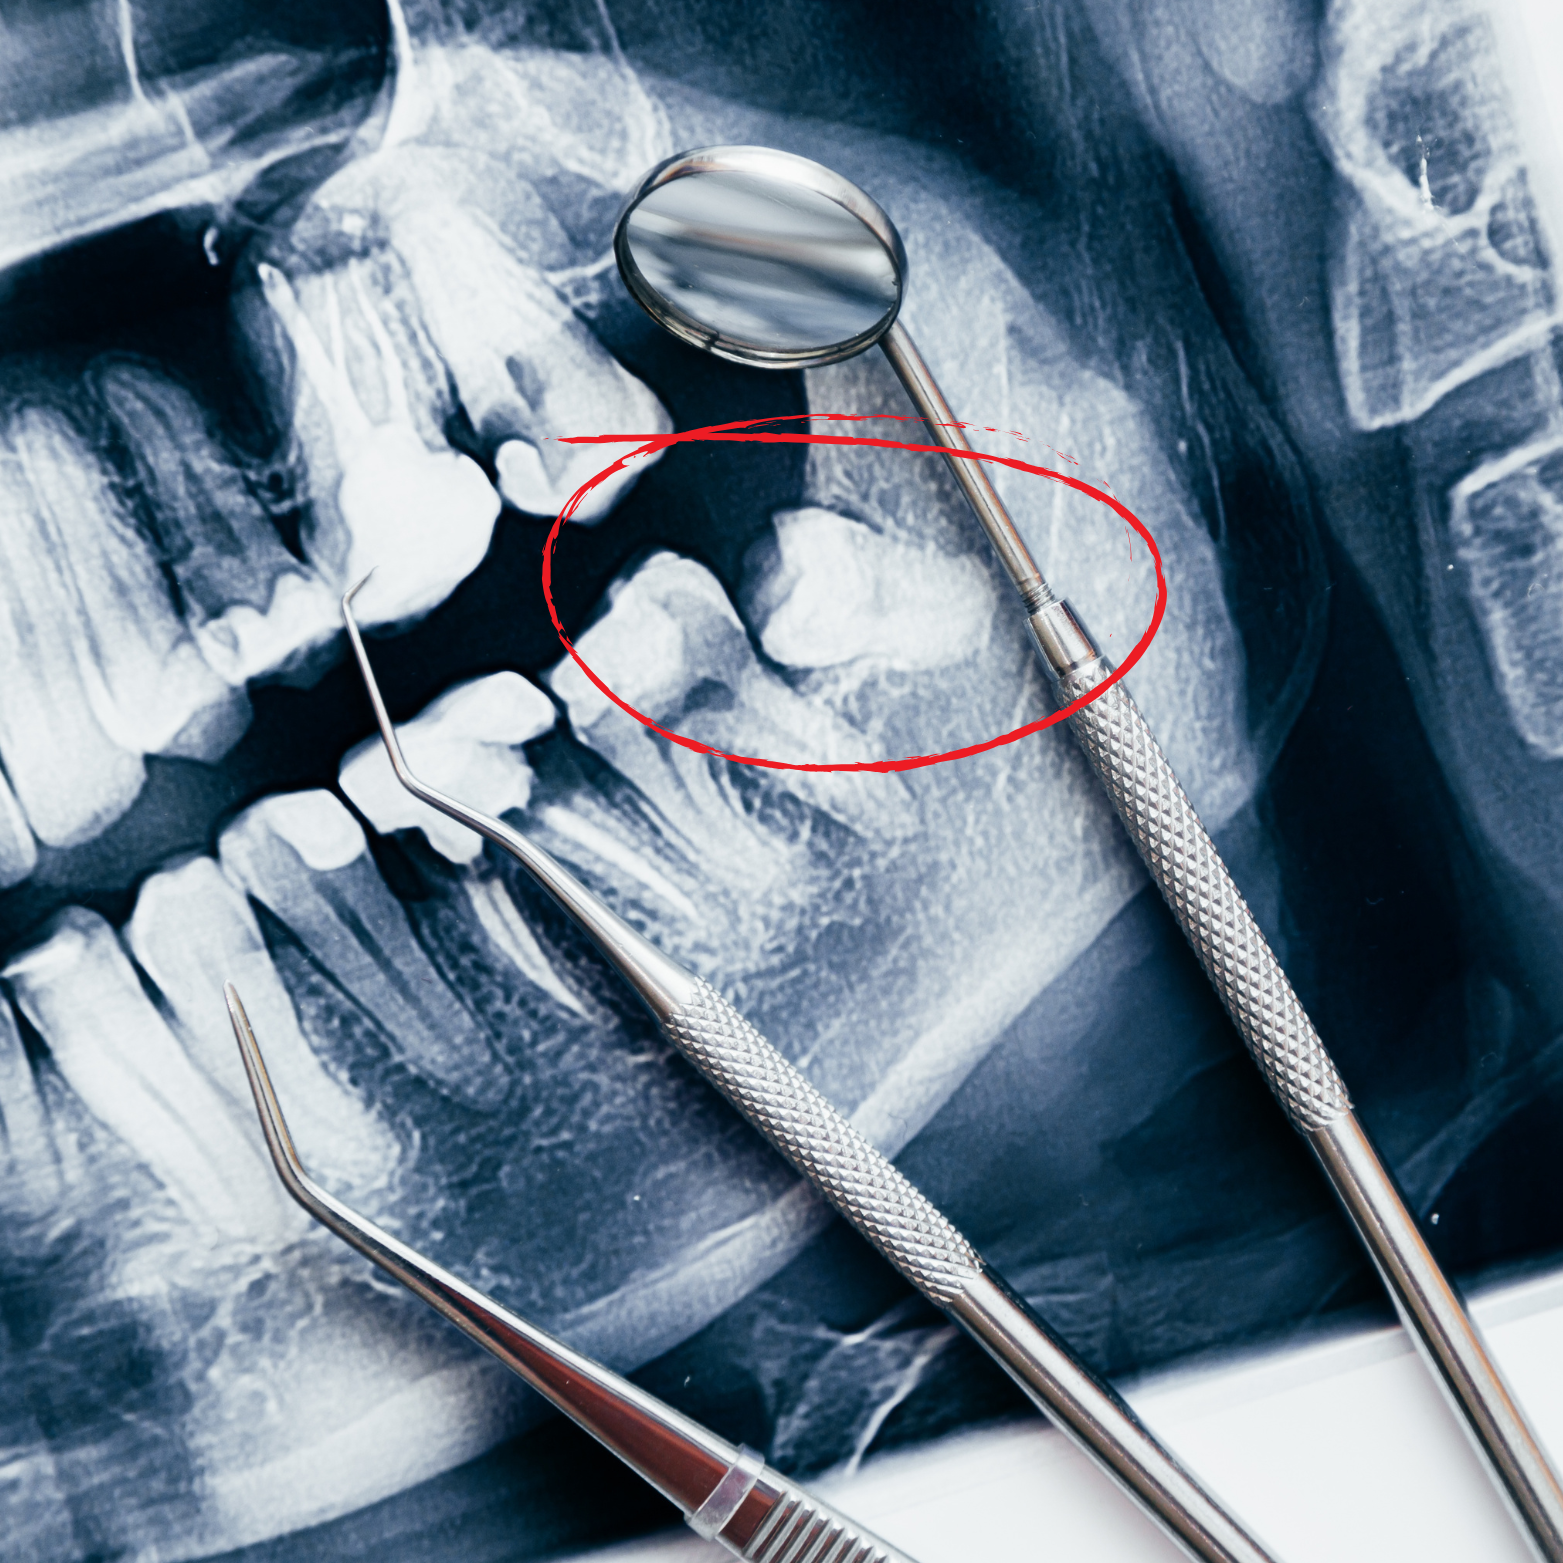

IMPACTED AND EMBEDDED SURGERY REMOVAL

Wisdom tooth removal is handled with gentle care and advanced technology to make the experience as comfortable and stress-free as possible — there’s no need to be scared. Our skilled team uses modern imaging and minimally invasive techniques to plan each extraction precisely.

From a warm, reassuring consultation to attentive aftercare instructions and follow-up, we’re here to support your recovery every step of the way, ensuring your comfort, safety, and confidence, so you can stay relaxed throughout the procedure.